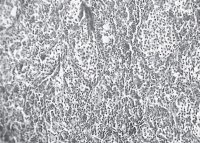

Ábra. 2. Adenocarcinoma kutya mell. H & E festés. SW. 20

Emlő adenokarcinóma kutyáknál (1. ábra) - rosszindulatú epiteiiális daganatot álló parenchima és stroma (4). Parenchyma saját tumorszövetben, a fő összetevője a tömegét, és meghatározzuk a növekedés és karakter. Strom beépített kötőszövet amelyben erek és idegek át. Parenchima kialakítva általában anyai szövet képződése során csíra. Stroma kialakítva a környező kötőszövet tumor csíra, amely ezt követően keresztülmegy egy bizonyos transzformációk hatása alatt a tumor parenchyma és képez vele egyetlen egész. Aljzatok adenokarcinóma falú, többnyire megfosztott izom membránok hullámos alakban, gyakran nyúlt zsúfolt vért. Nincs szigorú közötti megosztottság az artériák és vénák. Az utóbbit gyakran elé a hézagokat, amelynek fala áll az egyik endothelium. Az erek növekedését néha lemarad a turbulens proliferációs parenchyma (ábra. 2) a nem megfelelő vérellátás a tumorszövet gyakran merülnek fel elhalás (ábra. 3). Immunhisztokémiai vizsgálatok megállapították, hogy a daganat utal tumorok hormon-ösztrogén.